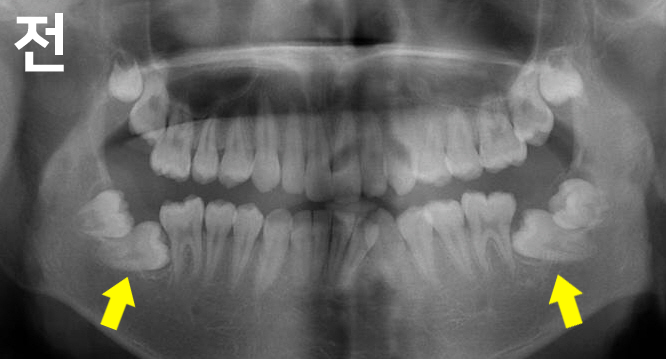

심한 어금니 매복으로 인해 내원하셨습니다.

부분교정으로도 해결할 수 있었으나 앞니 비뚤함도 개선 원하시어 전체교정으로 진행하였으며

교정 후 매복치가 올바르게 배열된 것을 확인할 수 있습니다.